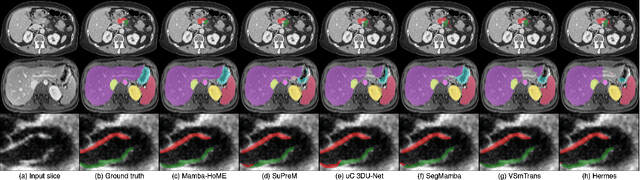

Abstract:In recent years, artificial intelligence has significantly advanced medical image segmentation. However, challenges remain, including efficient 3D medical image processing across diverse modalities and handling data variability. In this work, we introduce Hierarchical Soft Mixture-of-Experts (HoME), a two-level token-routing layer for efficient long-context modeling, specifically designed for 3D medical image segmentation. Built on the Mamba state-space model (SSM) backbone, HoME enhances sequential modeling through sparse, adaptive expert routing. The first stage employs a Soft Mixture-of-Experts (SMoE) layer to partition input sequences into local groups, routing tokens to specialized per-group experts for localized feature extraction. The second stage aggregates these outputs via a global SMoE layer, enabling cross-group information fusion and global context refinement. This hierarchical design, combining local expert routing with global expert refinement improves generalizability and segmentation performance, surpassing state-of-the-art results across datasets from the three most commonly used 3D medical imaging modalities and data quality.